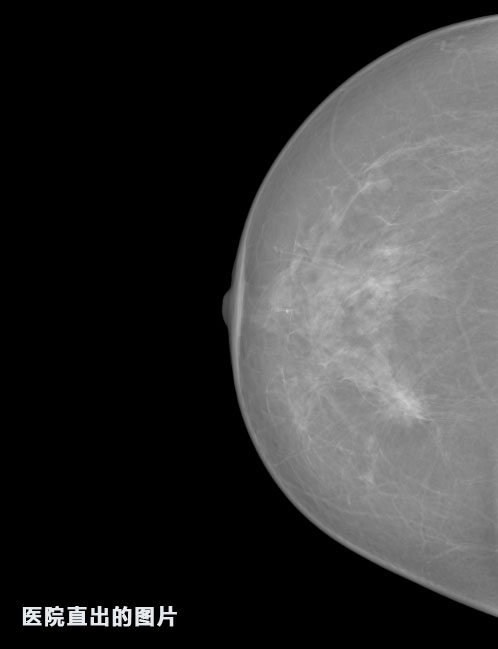

英特健康A(chǔ)I深度學(xué)習(xí)醫(yī)療圖像識(shí)別系統(tǒng)案例_乳腺

01.jpg

識(shí)別報(bào)告:

1.發(fā)現(xiàn)良性鈣化,可能性為19.88%---位置框指數(shù):[1796.0867 1359.8237 2058.1372 1582.5334]

2.發(fā)現(xiàn)惡意鈣化的可能性為15.18%---位置框指數(shù):[1789.4733 1365.9951 2063.7698 1576.0613]

3.發(fā)現(xiàn)惡意鈣化的可能性為12.45%---位于框指數(shù):[1859.3987 1422.3184 2006.5494 1528.2698]